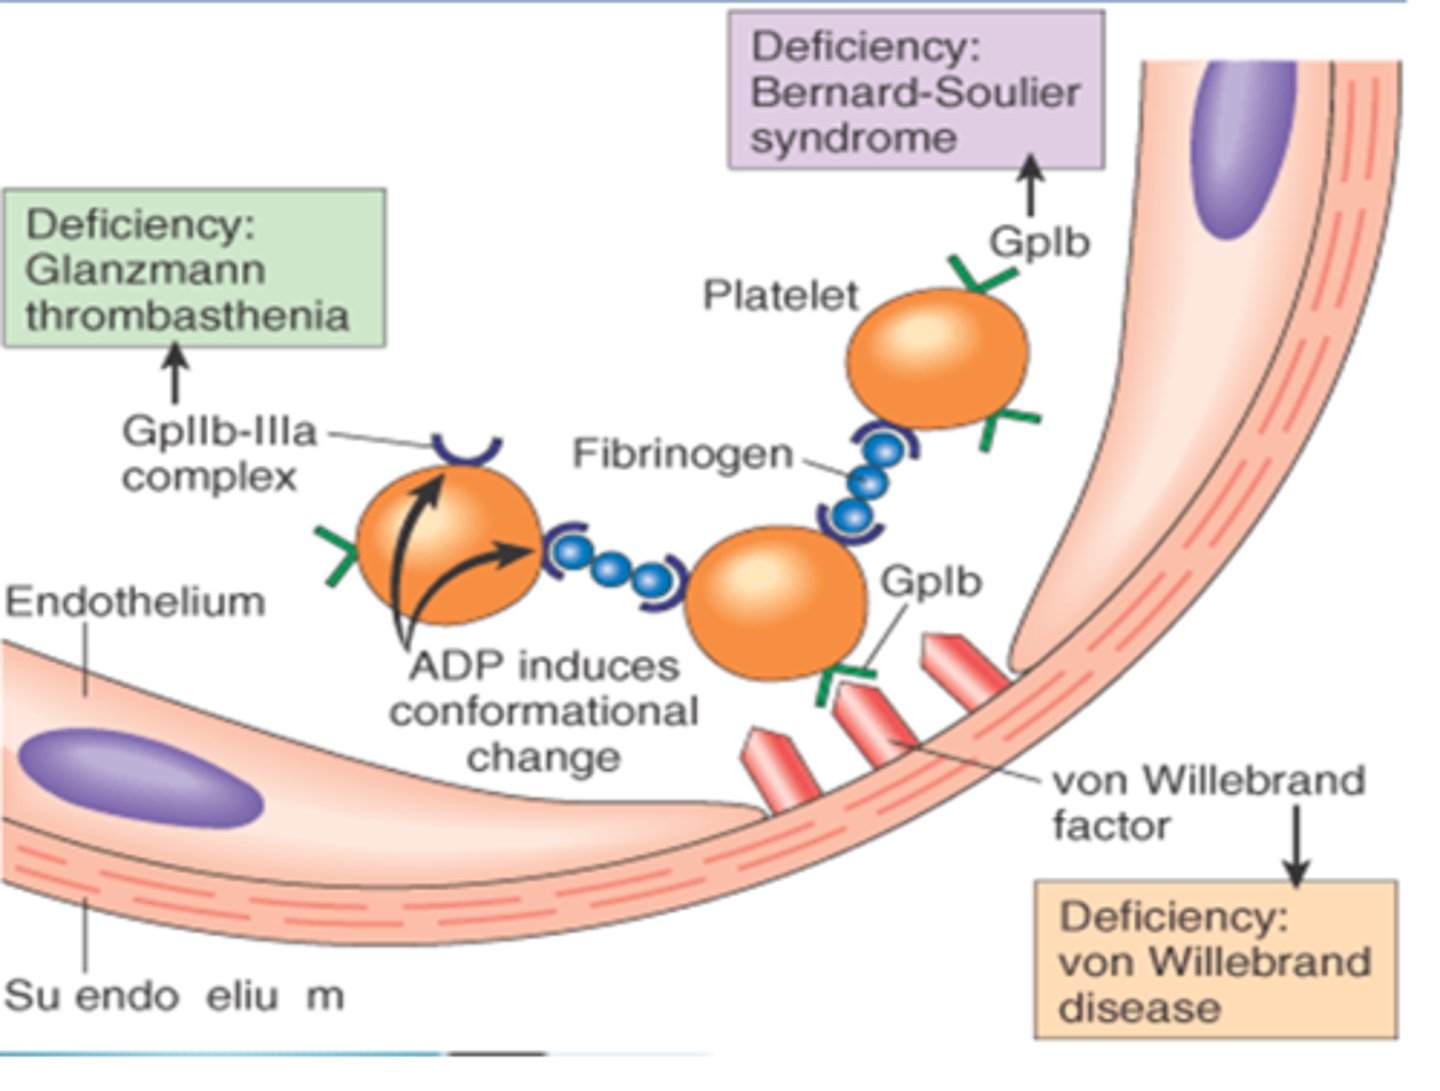

Mucosal bleeding and prolonged bleeding time

Glanzmann thrombasthenia

(defect in platelet aggregation due to lack of GpIIb/IIIa)